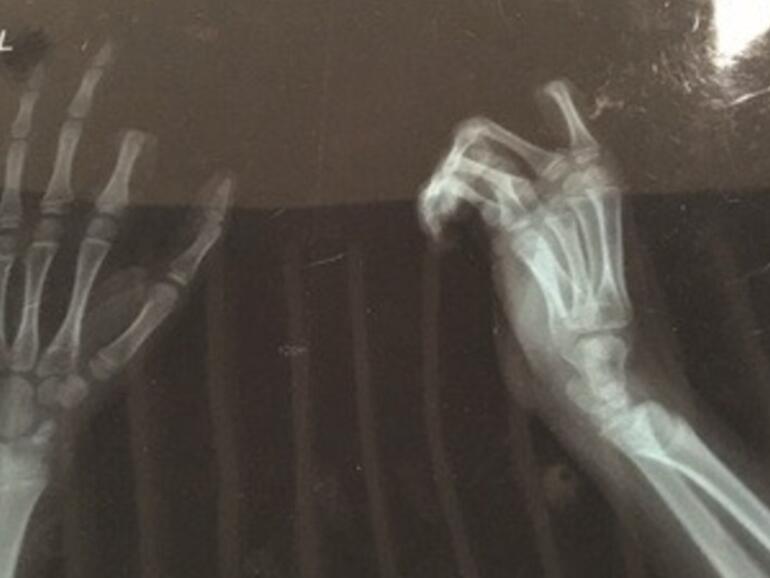

In einem Streit mit seinem Vater reichte es dem Jungen dann. Er wollte ihm die Nutzung des Smartphones verbieten. Aus Zorn griff das Kind zu einem schweren Küchenmesser und hackte sich, ehe der Vater reagieren konnte, einen Zeigefinger zu einem großen Teil ab.

Die Eltern brachten das Kind schnellstmöglich ins Krankenhaus, wo ein Team von Chirurgen den Finger wieder annähen konnte. Ob die dreistündige Operation gelungen ist, wird sich aber erst in einigen Tagen zeigen - fraglich ist, ob die Nerven funktionieren und die Blutgefäße den Finger versorgen können. Die Blutgefäße von Fingern sind naturgemäß schon sehr klein, bei Kindern sind sie so winzig, dass beim Zusammennähen nicht genau erkannt werden kann, ob sie verstopfen.

Jetzt wo du das Röntgenbild erwähnst, kommen mir Zweifel an der ganzen Geschichte. Warum sind zwei Hände auf dem Bild. Als ich mir die Hand gebrochen hatte, hat die gute Ärztin nur meine verletze Hand geröntgt.

Das ist zweimal die gleiche Hand :)

Okay ich hatte extra noch für Anzeichen das es die gleiche Hand ist gesucht. Könnt aber nicht erkennen das es zwei Bilder sind. Ich habe immer für jede Lage der Gliedmaße eigne Bilder bekommen. Wie dem auch sei, so eine Fall zeigt das es wirklich das man von Sucht reden kann, denn Süchtige handeln ja durchaus komplette verrückt.